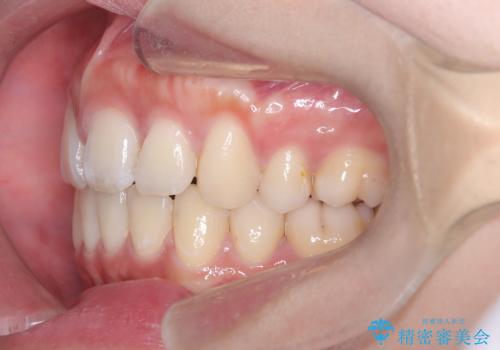

口元の突出感を解消し、横顔を美しく整えるワイヤー矯正

- 口元が出ていること(突出感)を気にされ、これを下げたいという主訴でご来院されました。精密な検査の結果、前歯を大きく後退させ、口元を改善するためには、スペースの確保が不可欠と診断しました。そこで、上下左右の第一小臼歯(4番目の歯)を計4本抜歯し、そのスペースを利用して前歯全体を奥へ移動させる抜歯矯正の治療計画を立案。確実な歯の移動を実現するため、ワイヤー矯正装置を使用しました。

今回の矯正治療では、口元の突出感を解消するためのスペースを確保するため、計画通り上下左右4本の小臼歯を抜歯しました。装置には、確実な歯の移動と細やかな調整が可能なワイヤー矯正を採用。抜歯によってできたスペースを最大限に利用し、前歯を奥へ、そして垂直的に慎重に移動させました。

治療の結果、長年のコンプレックスであった口元の突出感が大幅に解消され、横顔のライン(Eライン)が美しく改善しました。機能的な咬み合わせを確立すると同時に、患者様が望んでいた審美的な口元を獲得していただけました。